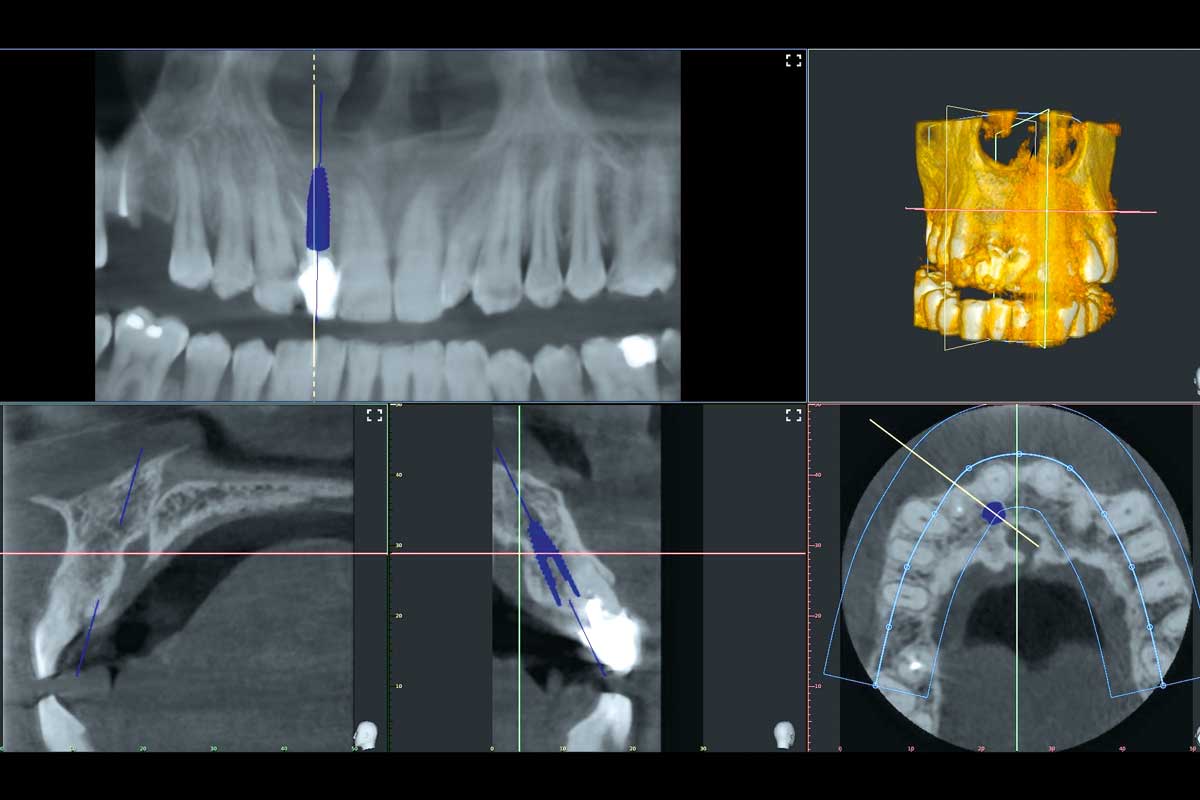

02/13 - The CBCT revealed adequate bone width and no pathology in the area, immediate implant placement was agreed

Immediate implant placement in the maxilla with contour GBR - Dr. K. Loukas

06/13 - Implant (3.3 BL x 12 mm) inserted in correct 3D prosthetic position, a 3 mm distance gap was left in the crestal section; Compared to CBCT apical concavity was more intense